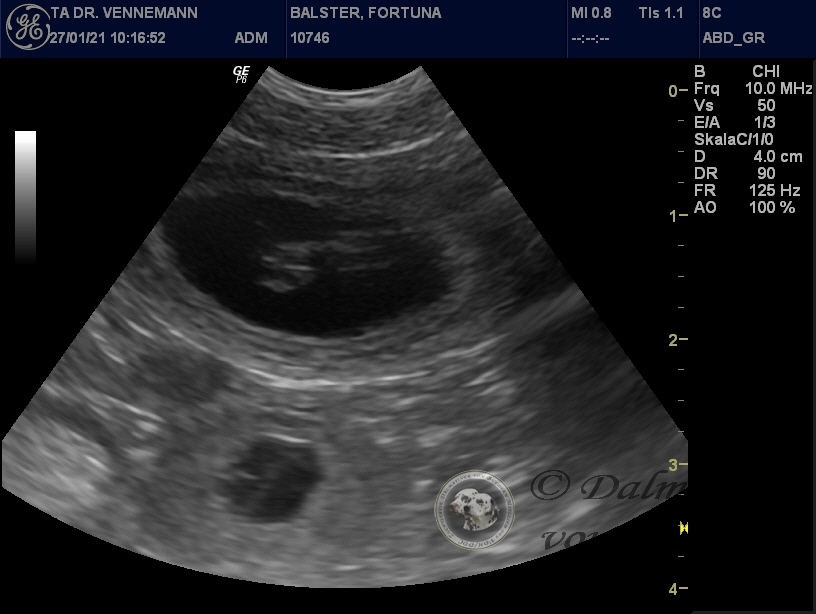

Der Ultraschall beim Tierarzt unseres Vertrauens hat uns Einblick in Selmas Bäuchlein gegeben. Deutlich sichtbar waren die schlagenden Herzchen der Winzlinge zu erkennen - immer wieder ein wunderbarer Anblick!